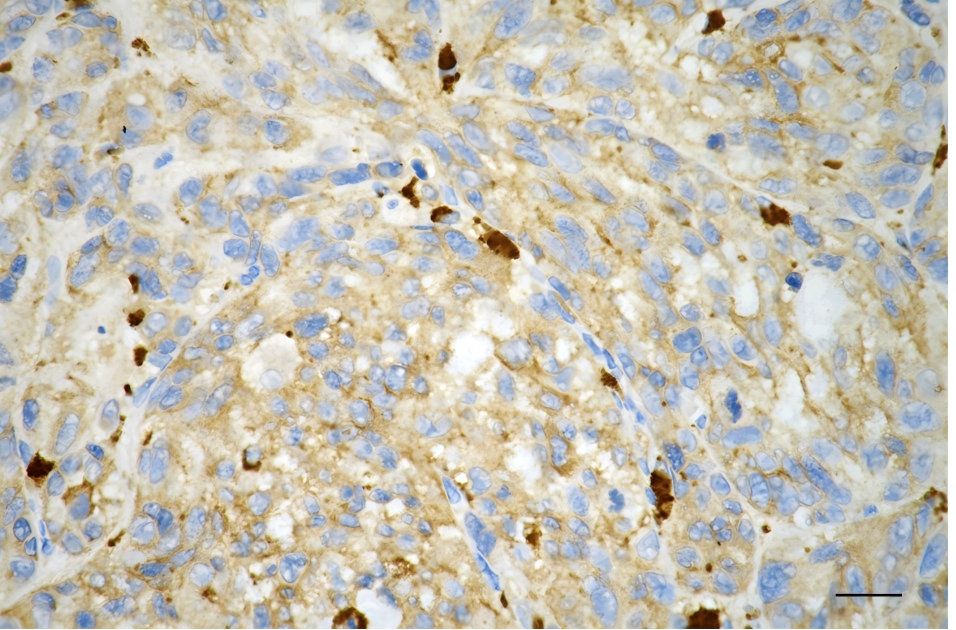

Immunohistochemistry was performed on paraffin-embedded human glioblastoma using PKC alpha antibody. Antigen retrieval was done in sodium citrate buffer (pH 6.0). DAB was used for detection, with hematoxylin counterstaining. Images were acquired using a Nikon Ci-L Plus microscope (40× objective). Scale bar: 25 μm.